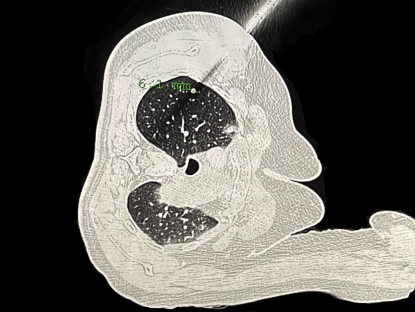

患者准备接受机器人导航穿刺手术。本文图片均为上海市东方医院供图

穿刺定位针到位。